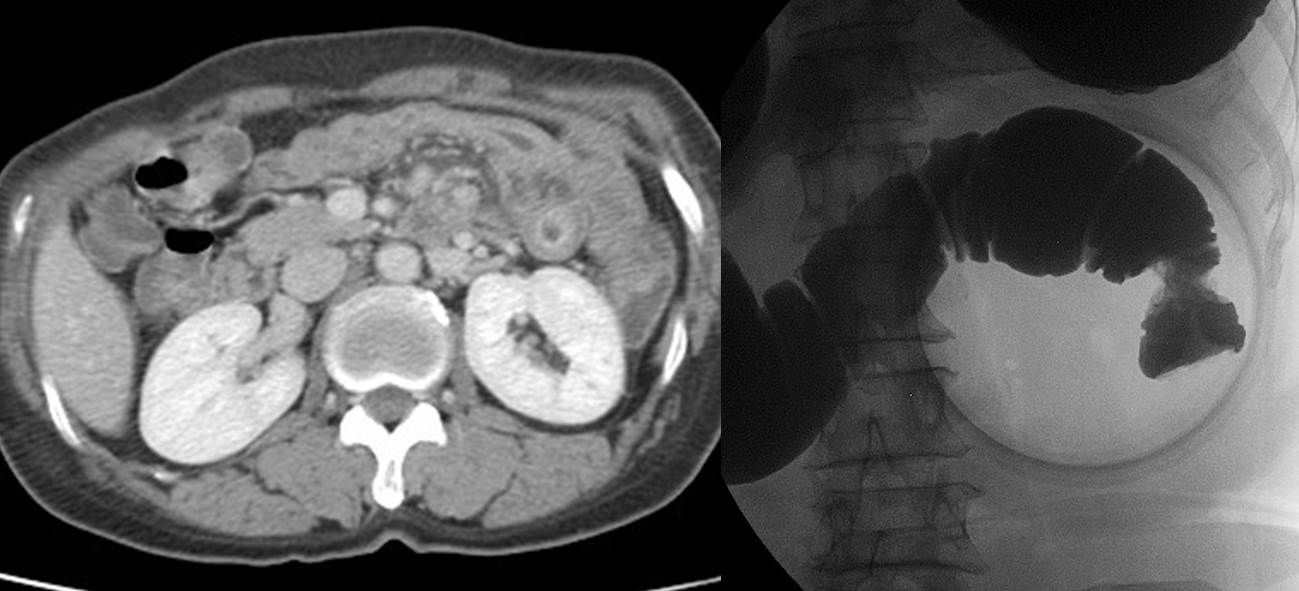

À§³»½Ã°æ°ú ´ëÀå³»½Ã°æÀ» µ¿½Ã¿¡ ¹ÞÀº ºÐÀÔ´Ï´Ù. ´ëÀå¿ëÁ¾ÀýÁ¦¼úÀ» ÇÏ¿´°í deep SM invasionÀ» º¸¿© ¼ö¼úÀû Ä¡·á¸¦ À§ÇÏ¿© ÀǷڵǾú½À´Ï´Ù.

´ëÀå¾Ï¿¡ ´ëÇÑ workupÀ¸·Î ½ÃÇàÇÑ CT¿¡¼­ À§º® ºñÈÄ¿Í ¸²ÇÁÀý ÀüÀ̰¡ ¹ß°ßµÇ¾î ù ³»½Ã°æ 4ÁÖ ÈÄ ´Ù½Ã À§³»½Ã°æÀ» ½ÃÇàÇÏ¿´°í À§ÁÖ¸§ ºñÈÄ¿Í ±íÀº ±Ë¾çÀÌ ¹ß°ßµÇ¾ú½À´Ï´Ù.

À§³»½Ã°æ Á¶Á÷°Ë»ç¿¡¼­ T cell lymphoma·Î ³ª¿Ô½À´Ï´Ù. 4ÁÖ °£°ÝÀÇ ³»½Ã°æ¿¡¼­ Å« ¸ð¾çÀÇ º¯È­¸¦ º¸¿´´Âµ¥, ÀÌ´Â ¸Å¿ì »¡¸® ÀÚ¶ö ¼ö ÀÖ´Ù´Â lymphomaÀÇ Æ¯Â¡ Áß ÇϳªÀÔ´Ï´Ù. »ç½Ç ù ³»½Ã°æ¿¡¼­ ¾à°£ÀÇ À§ÁÖ¸§ ºñÈİ¡ ÀÖ¾ú´ø °Í °°±âµµ ÇÕ´Ï´Ù.